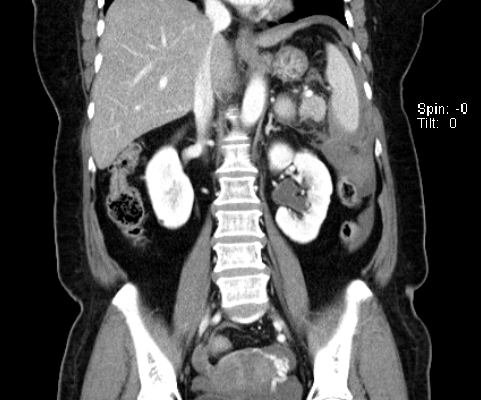

그래서 hydronephrosis 면 비뇨기과를 안가시고 왜 신장내과로 보냈을까하고 천천히 차트를 리뷰해보고 있는데, 이미 처음 응급실에서 찍었던 CT 에도 hydronephrosis 가 확인되었다.

요관을 따라서 내려가보면 중간에 결석이 보인다. 이분은 결석이 딱 걸려 있는데도 그 동안 통증이나 혈뇨 같은 다른 증상은 없었다고 한다.